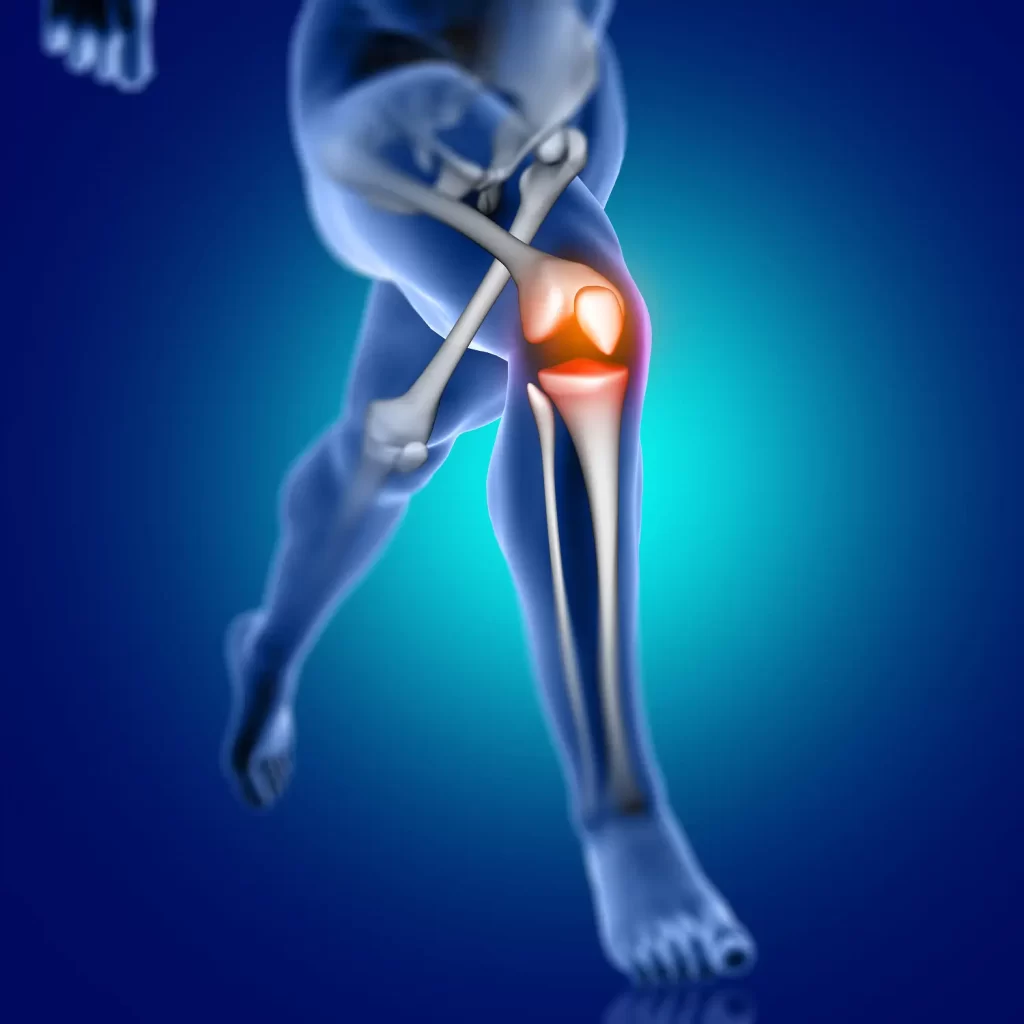

A artrose no joelho é uma das doenças articulares mais comuns e incapacitantes da atualidade. Caracterizada pelo desgaste progressivo da cartilagem, essa condição compromete a mobilidade, causa dor e impacta diretamente na qualidade de vida de milhões de pessoas em todo o mundo. Entender os sinais precoces, as causas e os tratamentos disponíveis é o primeiro passo para enfrentá-la com eficácia.

A artrose no joelho é uma doença degenerativa que afeta a cartilagem que reveste os ossos da articulação do joelho – fêmur, tíbia e patela. Quando essa cartilagem se desgasta, os ossos passam a friccionar diretamente uns contra os outros, gerando dor, inchaço e perda de mobilidade.

Com o avanço da doença, estruturas como ligamentos, músculos e membranas articulares também são comprometidas. Esse processo inflamatório reduz gradativamente a capacidade de caminhar, agachar ou subir escadas, comprometendo tarefas simples do dia a dia.

Crepitação (rangido) durante o movimento

Estalos, rangidos ou sensação de areia dentro do joelho são sinais de atrito ósseo. Esse sintoma, chamado de crepitação, está frequentemente associado ao avanço da artrose.